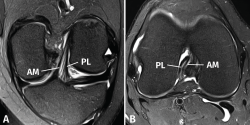

El protocolo de estudio por RM debe incluir secuencias en densidad protónica (DP) con supresión selectiva de la grasa en los 3 planos ortogonales. La valoración del LCA debe realizarse combinando la información de todos los planos. En el plano sagital, con frecuencia resulta complicado diferenciar tanto la anatomía fascicular como la inserción proximal. Los cortes coronales y axiales sucesivos son los más útiles para valorar con precisión la anatomía fascicular y las lesiones parciales del LCA (Figura 2).

Figura 2. Anatomía normal del ligamento cruzado anterior (LCA) en secuencias convencionales de resonancia magnética (RM). A: corte sagital potenciado en densidad protónica (DP) con supresión grasa que muestra en toda su extensión el trayecto del fascículo anteromedial (AM); B: corte coronal de RM potenciado en DP con supresión grasa que muestra la anatomía bifascicular. PL: fascículo posterolateral.

Las secuencias FSE 3D isotrópicas con diferentes nombres comerciales (Space®, Cube®, Vista®, MPV®...) permiten realizar reconstrucciones multiplanares, incluyendo planos oblicuos adaptados al trayecto del LCA(10,11,12,13,14). Estudios recientes muestran que estas secuencias tienen una precisión similar a las secuencias 2D convencionales en la valoración de las lesiones intraarticulares de rodilla. Sin embargo, las imágenes reconstruidas con estas secuencias FSE 3D muestran un mayor grado de distorsión geométrica que dificulta valorar específicamente las lesiones parciales del LCA. La realización de cortes milimétricos oblicuos 2D DP con campo de visión reducido en los planos coronal (siguiendo el trayecto del LCA) y axial (perpendiculares al LCA) permiten obtener imágenes de alta resolución espacial que facilitan una valoración más fiable de las lesiones parciales del LCA(15)(Figura 3).

Figura 3. Anatomía normal del ligamento cruzado anterior (LCA) en cortes oblicuos de resonancia magnética (RM). A: corte oblicuo coronal de RM potenciado en densidad protónica (DP) con supresión grasa adaptado al trayecto del LCA que muestra la anatomía bifascicular normal; B: corte oblicuo axial de RM potenciado en DP con supresión grasa perpendicular al trayecto del LCA que permite valorar el estado de ambos fascículos. AM: fascículo anteromedial; PL: fascículo posterolateral.